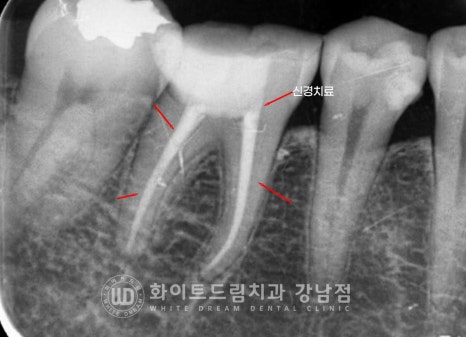

뿌리만 남아있는 치아들은 모두 신경치료를 받은 흔적이 보이는데

신경치료 후 크라운을 씌우지 않으셨고,

있던 크라운도 시간이 지나면서 탈락된 상태로 방치를 하셔서

치아가 모두 저작력을 버티지 못하고 부러져버린 상태인 것이죠.

뿌리만 남아있는 치아들은 모두 발치 후 임플란트를 식립하기로 하였고

하악 46번 인레이가 떨어진 치아는 신경치료 후 크라운치료를 진행하기로 했습니다.

이렇게 뿌리만 남은 치아들은

턱뼈까지 연결되어 있는 신경관이 겉으로 노출되어 있기에

잇몸뼈 내부 염증이 쉽게 발생하게 됩니다.